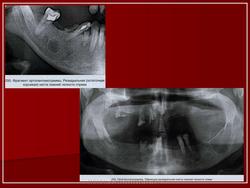

Это - типичный пример апикального просветления на рентгенограмме. Заметьте хорошо очерченную полость с отмеченной рентгеноконтрастной границей. Биопсия доказала , что это корневая киста. Заметьте соответствующий корням первого нижнего моляра.

Это - другой пример корневой кисты возникшей в результате некроза пульпы. Заметьте большую периапикальную рентгенопрозрачность, которая расположена очень близко к полости носа.

Эти рентгенограммы иллюстрируют примеры периапикальных просветлений. Диагноз корневой кисты или гранулемы может быть сделан только после гистологической экспертизы повреждения. Размер этих просветлений не показатель для диагностики, т.к. любое повреждение может давать вариаций в размере, отраженном количестве поглощенной кости в результате давления, создаваемым увеличивающимся процессом в кости. Островки ороговевающего эпителия, которые развились от одонтогенных остатков Malassez, могут также быть в периапикальной гранулеме без превращения в кисту. Врачи-эндодонты относят эти гранулемы к " бухтообразным кистам ". Окончательно корневая киста формируется зрелой коллагеновой соединительнотканной стенкой. Эта соединительная ткань - строма большинства кист, образующихся в челюстно-лицевой области. Избыточное количество фибробластов, основной клетки соединительной ткани, может быть обнаружено в пределах кистозной стенки и характеризуется темным окрашенным ядром в центре цитоплазмы (центры кристаллизации). Фибробласты замечены в пределах волнообразных волокон коллагена. Стенка, в целом, представляет собой воспалительный инфильтрат различной интенсивности. Лимфоциты - вообще наиболее видные клетки в инфильтрате и характеризуются темно-окрашенным ядром, которое занимает большую часть цитоплазмы. Плазматические клетки также присутствуют в большом количестве в стенках кист и главным образом замечены в хронических кистах. Плазматические клетки считаются "фабриками" иммуноглобулинов. Другие результаты гистологического исследования кистозной стены): Эритроциты (Стрелка 1) и области внутритканевого кровоизлияния, случайные спикулы дистрофии кости, многоядерные гигантские клетки и кристаллы холестерина.